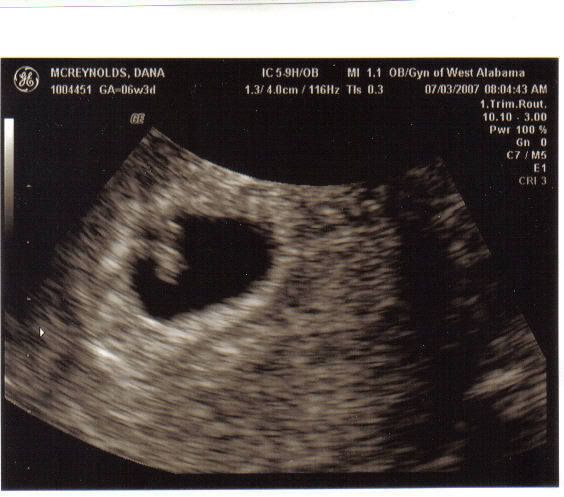

Ultrasound today - 6w3d

The ultrasound was WONDERFUL! We saw out little one as soon as the little wand was put in there. The little heart was pumping away, and then we got to hear it...you should have seen my husband's face. The heart rate was 123, which is great for how far along I am. The baby measured right on, so everything looks great smile.gif I go back in 4 weeks to se the doctor, but no ultrasound until between 18 and 22 weeks. So yeah, it went very well! I'm so glad it's over because I had nightmares all night long wacko.gif Anyway, I shall post pictures tonight.

Danalana replied: user posted image

BabyOwen427 replied: Awe! I love your little blob! laugh.gif laugh.gif

What a beautiful little peanut! I'm so glad things are going so well for you this time!!

I showed my mother and she was just beaming with joy. Then she said "I can't decide who she/he favors most" laugh.gif I think it favors Richard right now tongue.gif